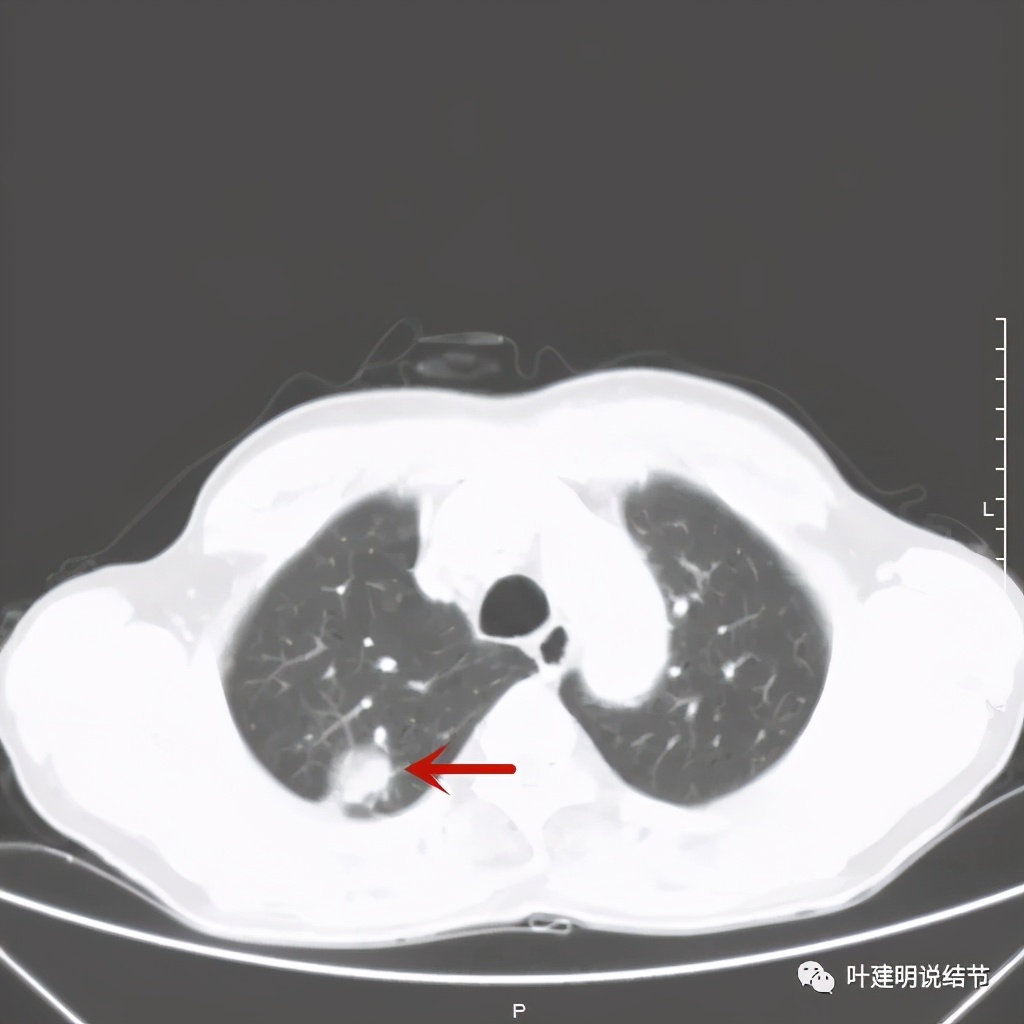

金华的某A,今年66岁,前几天在当地医院查胸部CT平扫发现右上肺占位,当时来找我看时,我想首先肺内占位是要警惕肺癌的,建议其住院进一步做增强CT,以及完善其他相关检查。其中增强CT报告示:右上叶约7*6厘米的肿块,增强后显著强化。而且某A曾于2018年5月在本院做过肺部CT,当时右上肺没有病灶的。我们先来看这次的CT图像:

红色示病灶,绿色示病灶旁边有磨玻璃成分,但较为模糊;蓝色箭头示病灶与胸膜间有牵拉,但力度不太够。

总体上感觉,病灶比较大,不规则,不是圆形或圆形生长,周围有模糊磨玻璃影(考虑炎性渗出性?),虽有胸膜牵拉,但力度不够;增强有显著强化。病灶明显却无明显临床症状,普通感染是不像的,要么是结核,要么是肺癌。但肺癌的话,在2年前没有,2年内长到这么大,恶性程度应该很高,但其纵隔淋巴结却没有明显肿大。而且病灶的边缘部分过于光滑,没有见到肿瘤的细毛刺,膨胀性也不够。整体看病灶有点像“腰子”形,弯弯曲曲的。所以我的感觉更倾向结核性。查了肿瘤筛查指标如下: